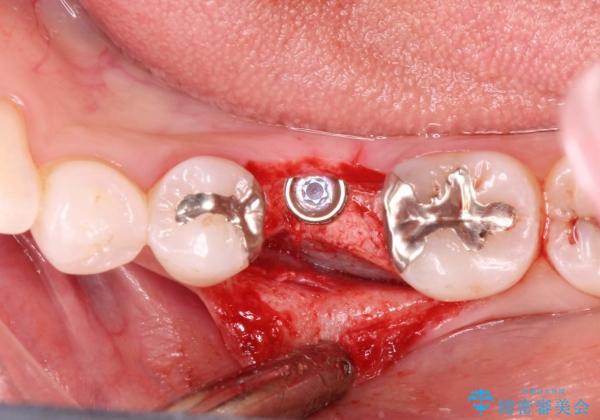

- 治療計画

- 保存不可能な歯の抜歯後、待時にてインプラントを埋入、2回法にて咬合回復を計画した。

インプラントの種類:strauman SLActive

- 外科手術のため、術後に痛みや腫れ、違和感を伴います